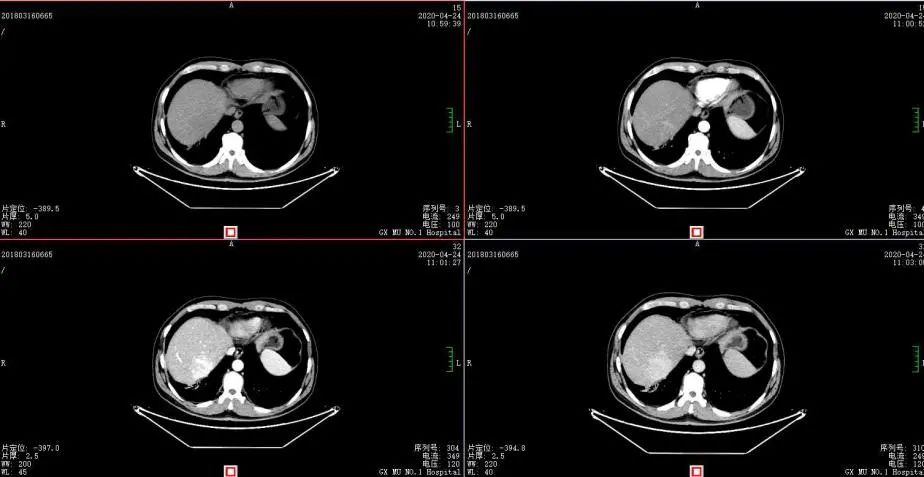

2020年4月复查:持续PR

增强CT示:肝硬化

肝异常强化灶

考虑酒精性肝硬化可能性大,未基线使用替吉奥维持治疗。

胃癌并肝转移化疗后,肝内转移灶大致同期;